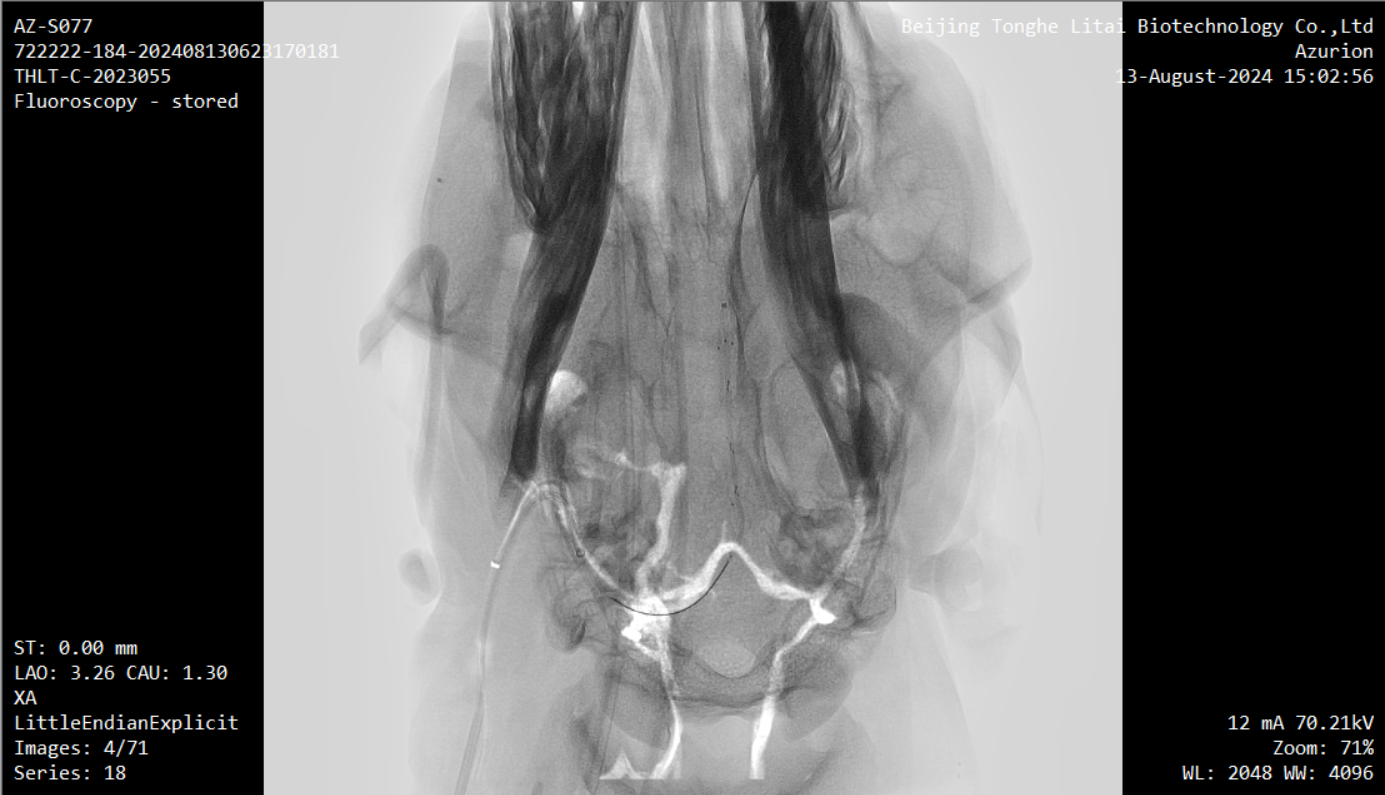

据介绍,本次试验是在前期两项试验基础上取得的进一步成果。内容包括涉及将无线传输设备植入实验动物皮下,并将采集到的介入式脑电信号通过无线传输设备传出,实现了稳定、高效的信号传输;通过介入手术将先前导入羊颅内血管壁上的介入式脑机接口传感器安全取出,整个过程在DSA造影引导下进行,确保了手术过程的安全性。